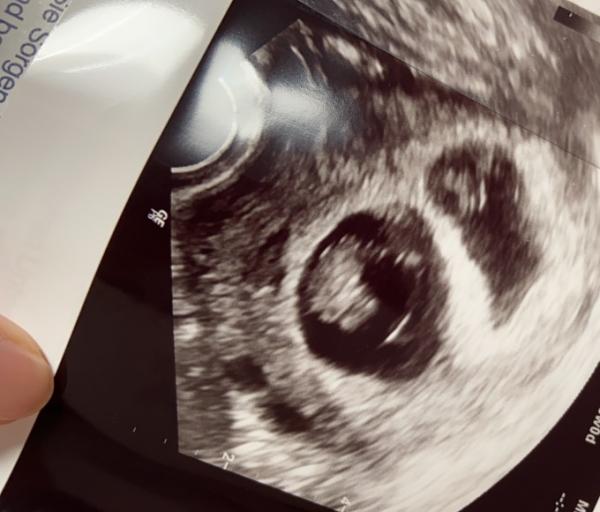

Hatte heute meine erste offizielle Vorsorge. Beim letzten Termin war ja eine Fruchthülle mit Embryo inkl Herzschlag zu sehen und eine Fruchthülle „nur“ mit Dottersack, bei 5+6. Heute bei 7+6 dann zwei Babys mit kräftigem Herzschlag, eins ist drei Tage weiter als das andere, das macht aber laut Ärztin nix und kann sich auch noch ändern. Bin happy, aufgewühlt... alles zusammen. Sollte ja eigentlich „EIN“ Nachzügler werden Weiß jemand von euch, ob bei ü35 die Nackenfaltenmessung von der KK übernommen wird? Es war schwierig beide aufs Bild zu bekommen... Liebe Grüße in die Kugelrunde

Danke ihr Lieben!! Habe gerade gesehen, dass das Foto hochladen nicht geklappt hat, daher zweiter Versuch! Allen ein schönes Wochenende

Bild zu